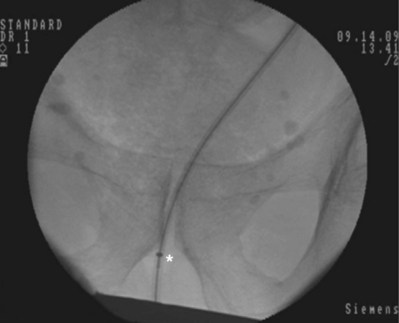

An alternative technique that relies more on fluoroscopic visualization for stent placement and less on cystoscopic visualization is often advantageous when dealing with more challenging stent placements such as impacted ureteral stones or malignant obstruction (Figs. 7-7 through 7-16).

Figure 7–7 Flexible cystoscopy is used to locate and, under fluoroscopic guidance, pass a floppy tip guidewire through the ureteral meatus.

After obtaining bladder access with either a flexible or rigid cystoscope, a floppy-tip guidewire is advanced into the ureteral meatus and coiled in the renal pelvis using fluoroscopy, the cystoscope is then removed and an 8- to 10-Fr coaxial dilator is advanced under fluoroscopy until the 10-Fr sheath is at the urethral meatus. The 8-Fr internal dilator is removed, leaving a conduit (10-Fr outer sheath) through which to advance the stent.

The ureteral stent is then advanced over the guidewire through the 10-Fr sheath by using a pusher with a small fluoroscopically visible metal band at its tip. The metal tip pusher is advanced under fluoroscopic control to the upper border of the pubic symphysis in male patients and lower border in female patients, while stabilizing the position of the lower end of the stent. The 10-Fr sheath and subsequently the guidewire are removed, allowing the stent to curl in the bladder.